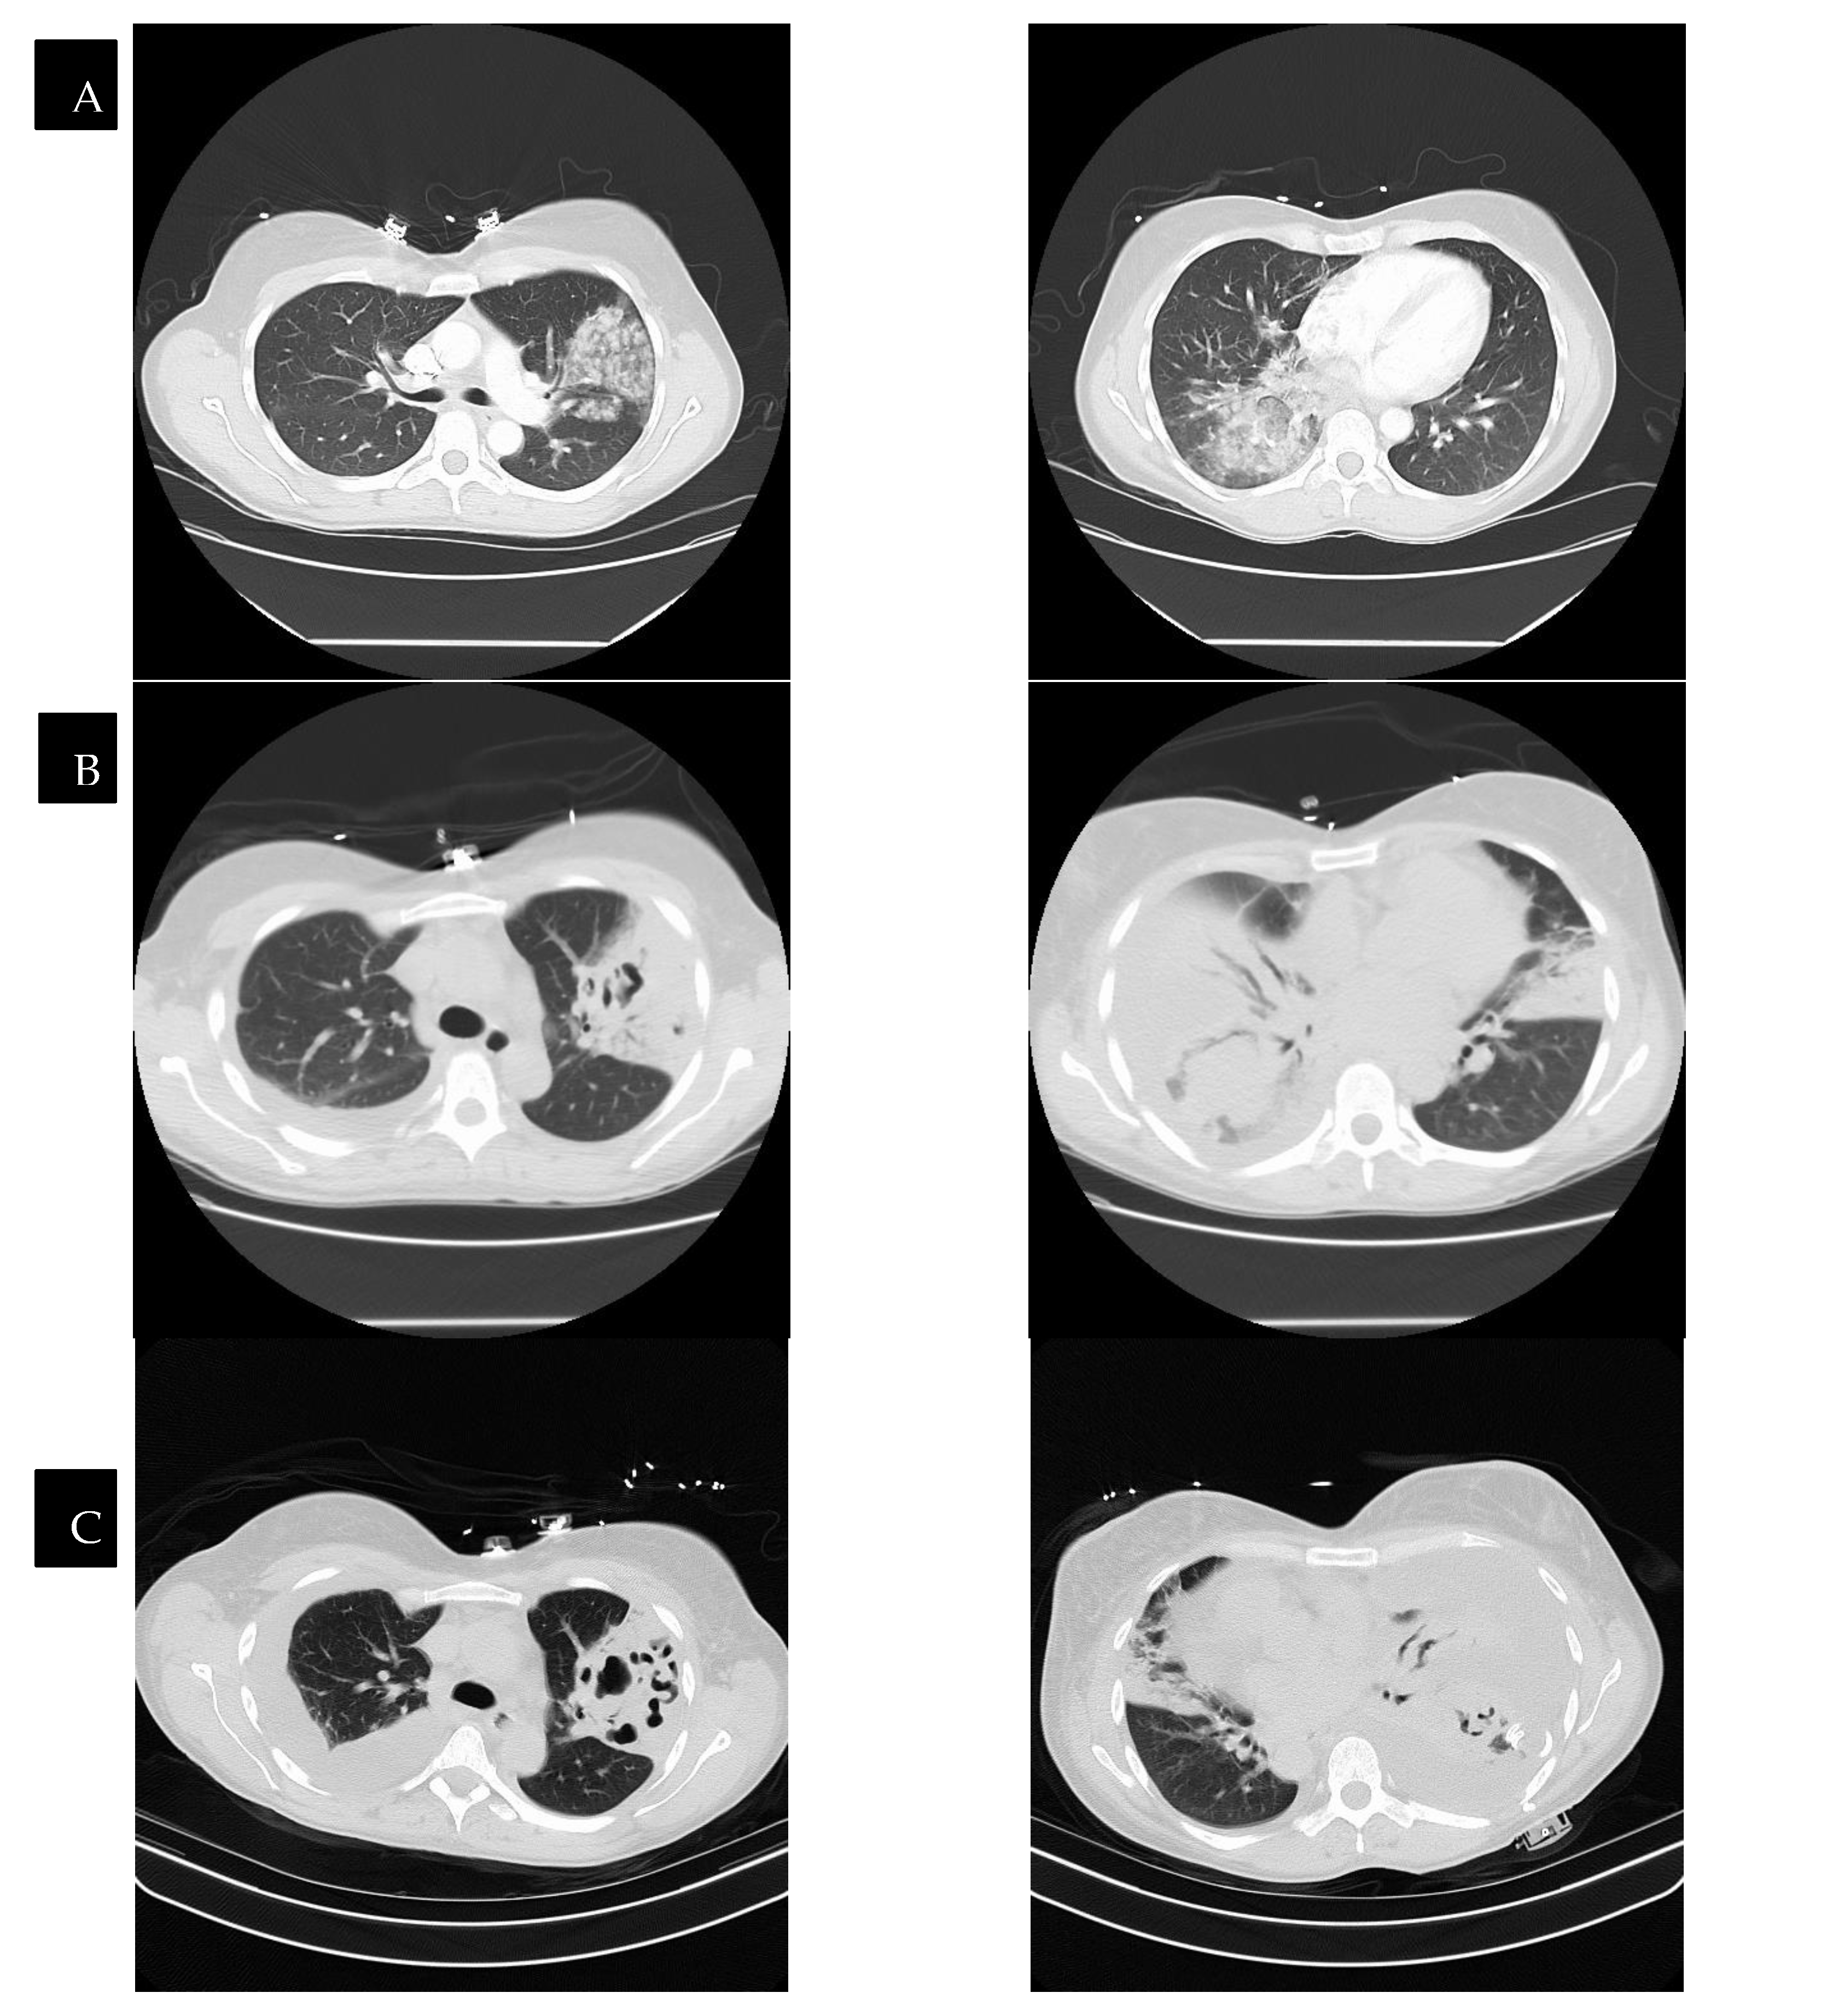

8. Radiology